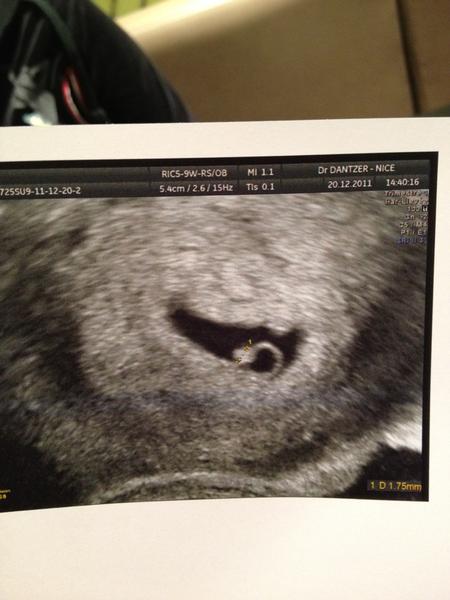

Je vous met mon écho,c'est le petit point blanc a coté du cercle

• mini nous 5 semaines.jpg

mini nous 5 semaines.jpg